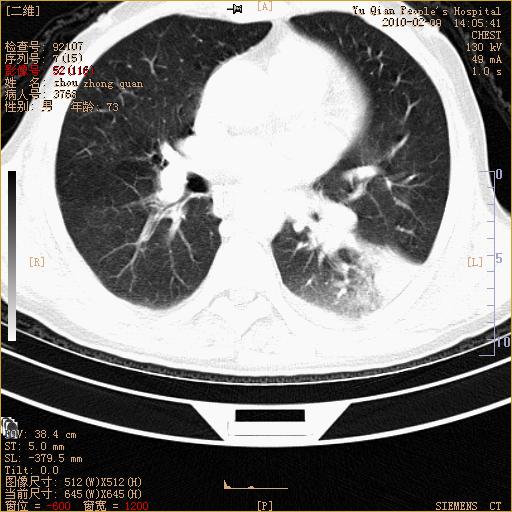

男性,73岁,咳嗽咳血数天,诊为肺ca伴左肺下叶后段阻塞性炎症、肺不张妥否?

左下肺中央型肺癌伴结段形肺不张,左侧胸腔积液,纵隔内见部分增大淋巴结(反应性增生或转移)

左下基底干支气管明显变窄。

左肺下叶基底段支气管狭窄,左肺门增大,左肺下叶团片状病灶。中心型肺癌伴柱塞性炎症可能大,建议支气管镜检查。

左下肺中央型肺癌伴节段性肺不张,左侧胸腔积液,纵隔内见肿大淋巴结

左下基底段支气管变窄。建议进一步纤支镜检查。

1、左肺下叶后基地段肺癌伴阻塞性炎症,左下肺门淋巴结转移。2、左侧胸腔积液。